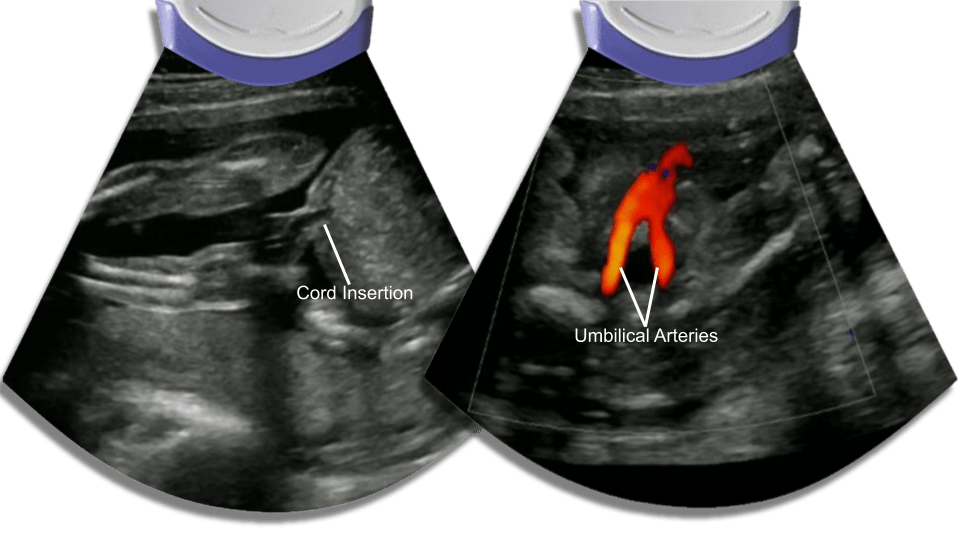

Cord Insertion

The normal umbilical cord has 3 vessels, two arteries and one vein. The umbilical arteries go down pass the bladder into the bilateral iliac arteries and the umbilical vein travels up into the liver. good place to rule out omphalocele and and bladder extrophy.

Bladder

The bladder could be empty, it fills every 30 to 45 minutes or so. look for bladder extrophy, keyhole bladder which indicate posterior urethral valves.